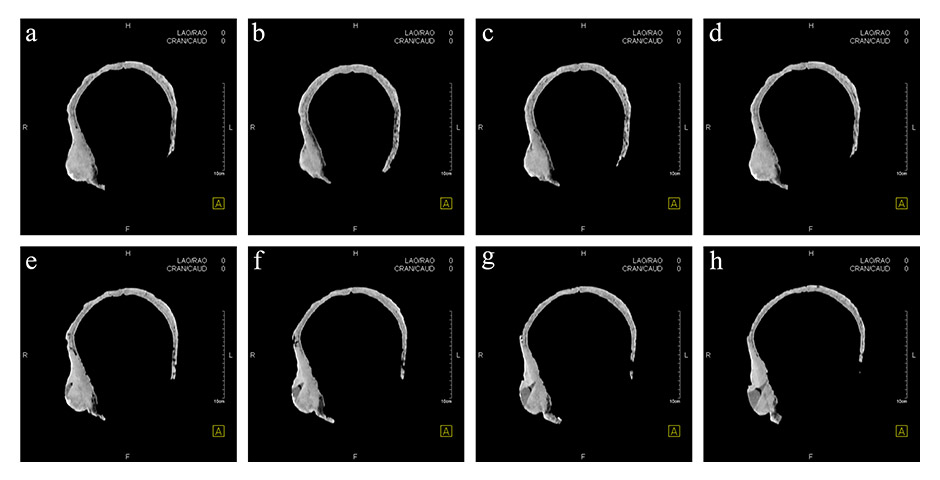

Figure 5

Horizontal computed tomography cross-sections of the skull. Selected representative slices.

The remains are well preserved. Morphological examination of skull and pelvis clearly classify the individual as female. The age at death was between 30 and 50 years. There is an intensely calcified bone proliferation at the right side of the os frontalis (fig. 2). Plain X-ray and CT imaging show a large (5.3 x 3 x 8.7 cm) sclerotic lesion in the area of the right temple with a partly bulging appearance (fig. 4). Figure 5 shows representative slices of the admission CT. A differentiation between tabula interna, diploë and tabula externa is not possible in major parts of the lesion. The inner boundary of the lesion shows multiple smooth-edged irregularities. There is a diffuse thickening of the right skull vault (right 7 mm, left 4 mm). The left skull vault presents a mix of sclerotic areas and areas with normal appearance with a clear differentiation between tabula interna, diploë and tabula externa. CT imaging and plain X-ray show a wedge-shaped area in the centre of the lesion that is filled with material of lower X-ray density than the adjacent bone (figs 5 and 6). Histology shows mature organised lamellar bone tissue with ordered formation of trabeculae (figs 7–9). No pathological alterations were found in the postcranial bones.

There are already several known cases of benign tumours in ancient populations. Brothwell and Sandison [10], for example, described a case of ivory osteomata in a Roman Egyptian skull. Our study presents a very unusual case of multiple osteosclerotic lesions in an Iron Age skull from Switzerland. It is the oldest known case with this kind of pathology worldwide. Analysis with various investigative methods leads to a differential diagnosis. The CT image showed that a piece of bone had been removed from the lesion earlier (fig. 5e‒h). The sampling point was then carefully reconstructed so that there was no visible trace left. It is not clear when this reconstruction of the earlier sample was done and the person who took the sample is also unknown. This work was never published or presented. In the 1950s and 1960s, one of the anthropologists in Switzerland was Erik Hug [31, 32]. His work on bone material included reconstructions just like the one in the Hochdorf skull. This could indicate that the earlier bone biopsy was performed by Erik Hug.